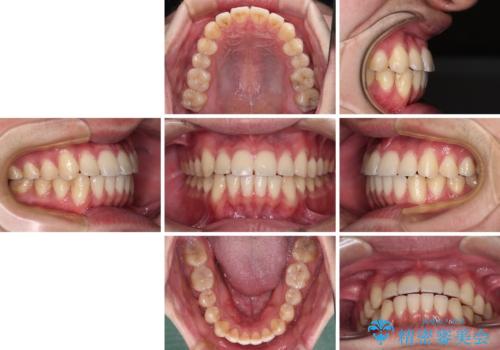

八重歯と前歯のクロスバイト ワイヤー装置で短期間矯正

- 八重歯を気にして来院された患者様です。

上顎側切歯(前から2番目の歯)が内側に転位している歯列は、インビザラインでは排列が困難であることが多いため、期間を短く、より良い仕上がりとするため、ワイヤー装置にて矯正治療を行うこととしました。

治療開始の頃は、食事や歯磨きが慣れず、装置が頻繁に脱落しましたが、2,3ヶ月ほどで慣れ、その後は1年ほどで治療を終えることができました。